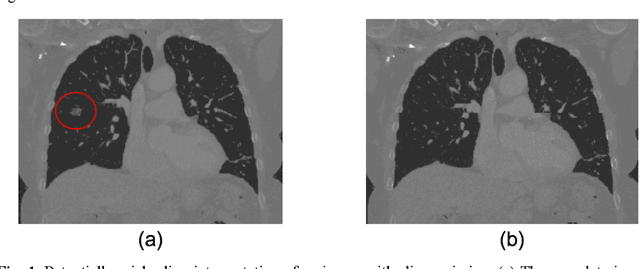

Abstract:The accuracy of predictive models for solitary pulmonary nodule (SPN) diagnosis can be greatly increased by incorporating repeat imaging and medical context, such as electronic health records (EHRs). However, clinically routine modalities such as imaging and diagnostic codes can be asynchronous and irregularly sampled over different time scales which are obstacles to longitudinal multimodal learning. In this work, we propose a transformer-based multimodal strategy to integrate repeat imaging with longitudinal clinical signatures from routinely collected EHRs for SPN classification. We perform unsupervised disentanglement of latent clinical signatures and leverage time-distance scaled self-attention to jointly learn from clinical signatures expressions and chest computed tomography (CT) scans. Our classifier is pretrained on 2,668 scans from a public dataset and 1,149 subjects with longitudinal chest CTs, billing codes, medications, and laboratory tests from EHRs of our home institution. Evaluation on 227 subjects with challenging SPNs revealed a significant AUC improvement over a longitudinal multimodal baseline (0.824 vs 0.752 AUC), as well as improvements over a single cross-section multimodal scenario (0.809 AUC) and a longitudinal imaging-only scenario (0.741 AUC). This work demonstrates significant advantages with a novel approach for co-learning longitudinal imaging and non-imaging phenotypes with transformers.